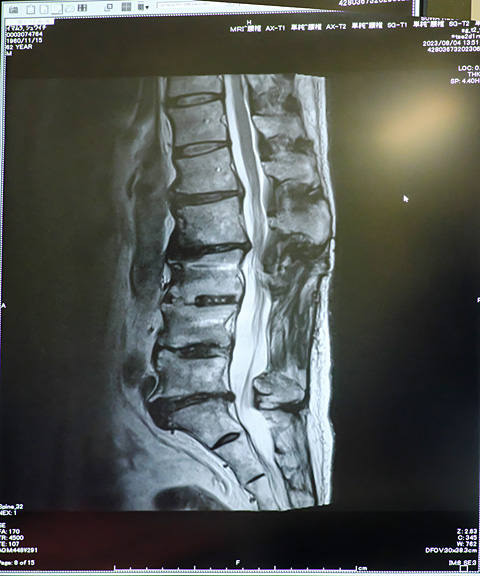

諏訪の日赤病院へ。5日はMRIの撮影に行く。

7日が検査結果と診察日。

なおみもボクも東京でCTの検査して異常なしだった。たぶん二人の腰痛の原因は外科的なものではないと思ったので間欠性跛行の検査を希望していた。かかりつけの医者に「日赤なら設備が整っている」と言われてしぶしぶ整形への紹介状をもらった。初診の日,担当医に「間欠性跛行」の検査を受けたいと申し出た。

「何ですか?それ」

と医者は答えた。これが地方の総合病院のレベルだろう。そして二人ともMRIの検査を勧められて今日に至る。

なおみの背骨は

「健康な人の見本にしたい。」

と医者が言う状態。

ボクの背骨は狭窄症の手術をした骨の上と下に変形が見られたが,どちらも現在の痛みや痺れとは無縁だと診断された。当たり前である。場所がぜんぜん違う。

「現在の医学ではお二人とも原因は特定できません。」

治療の継続を断って再びかかりつけ医に紹介状を書いてもらった。東京での4年間の治療で分かり切っていたことを再び確認するだけに終わった。

二人揃って痛みと痺れのために10分間が立っていられない。その現実だけが残った。